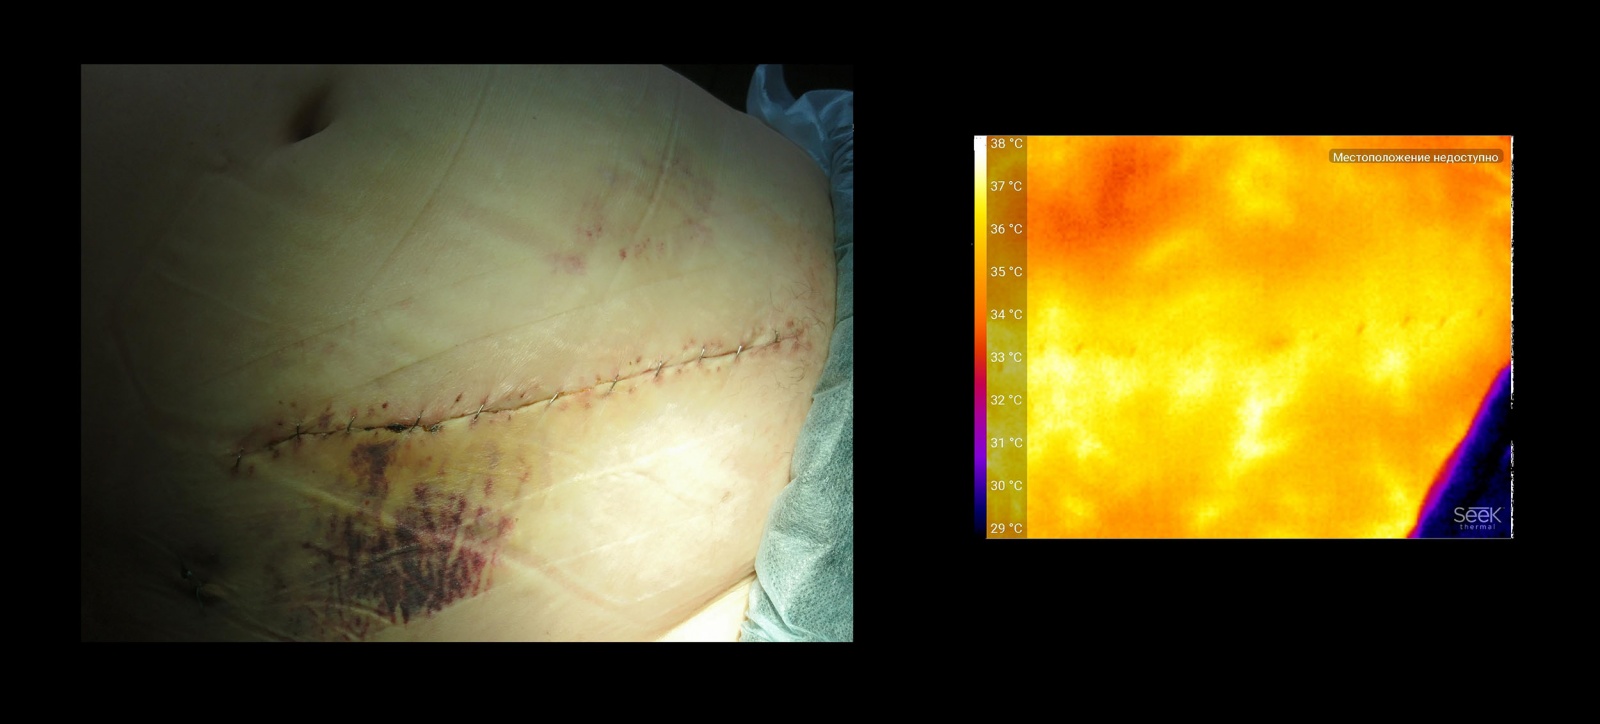

Вот так выглядит рана на момент конца операции:

Некоторое снижение температуры связано с рассечением части сосудов, питающих подкожную клетчатку и кожу. К тому же ткани, подвергшиеся воздействию при операции, имеют свойство отекать (природа отека несколько отличается от воспаления, сосуды при этом не расширяются, а сдавливаются жидкостью извне), Дополнительная ишемизация (ослабление притока крови) происходит из-за лигатур, которыми формируются швы — они дополнительно сжимают ткани.

Кроме описанных факторов, снимок иллюстрирует равномерность затягивания лигатур, а так же место истончения подкожной клетчатки (косая складка в верхней части фотографии). Она длительно существует из-за специфической деформации позвоночника пациента.

Этот снимок сделан через 10 дней после операции. Кожа ушивалась не лигатурами а специальными скрепками — они не создают ишемии. Тепловые «узоры» на коже в отдалении от шва, вероятно, соответсвуют крупным сосудам подкожной клетчатки. Пациентка длительно получала терапию стероидными препаратами, типичный побочный эффект — увеличение подкожной клетчатки туловища в объеме и повышенная склонность этого жира накапливать в себе воду. Жировые отложения — хороший термоизолятор — они слабо прогреваются от более глубоких тканей, к тому же достаточно мало производят тепла, но зато сосуды на фоне такой клетчатки очень контрастные.

Большая рана по средней линии тела «чистая», она зажила в обычные сроки без каких-либо проблем. Ушита лигатурами — некоторое снижение температуры ровно по линии шва заметно (почему так может быть — уже сказано выше). То, что кожа на ближайших ко шву 2-3 см теплее, чем в других зонах, возможно, артефакт от ношения самоклеящейся синтетической повязки — она создает «эффект парника», а снимок сделан непосредственно после ее удаления. Зато небольшая рана сбоку — там, где была колостома, — отстает на несколько градусов. Это связано с ее «условной инфицированностью» — небольшой объем тканей, контактировавший с кишечной флорой потерял жизнеспособность, и в процессе заживления происходит «отторжение» этих клеток организма. Приятным открытием оказалось то, что зарубежные ученые статистически подтвердили — при наличии бактериальной флоры температура шва падает.